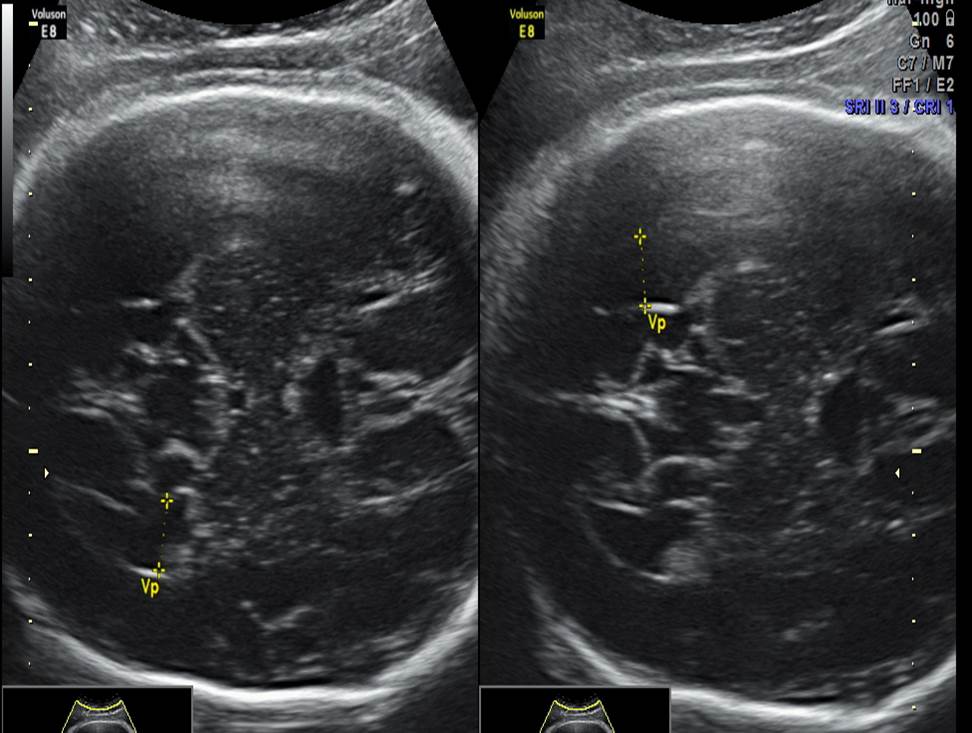

Проанализируйте изображения и видео-клипы плода в 20 недель, установите диагноз

Проанализируйте изображения плода в 20 недель, установите диагноз